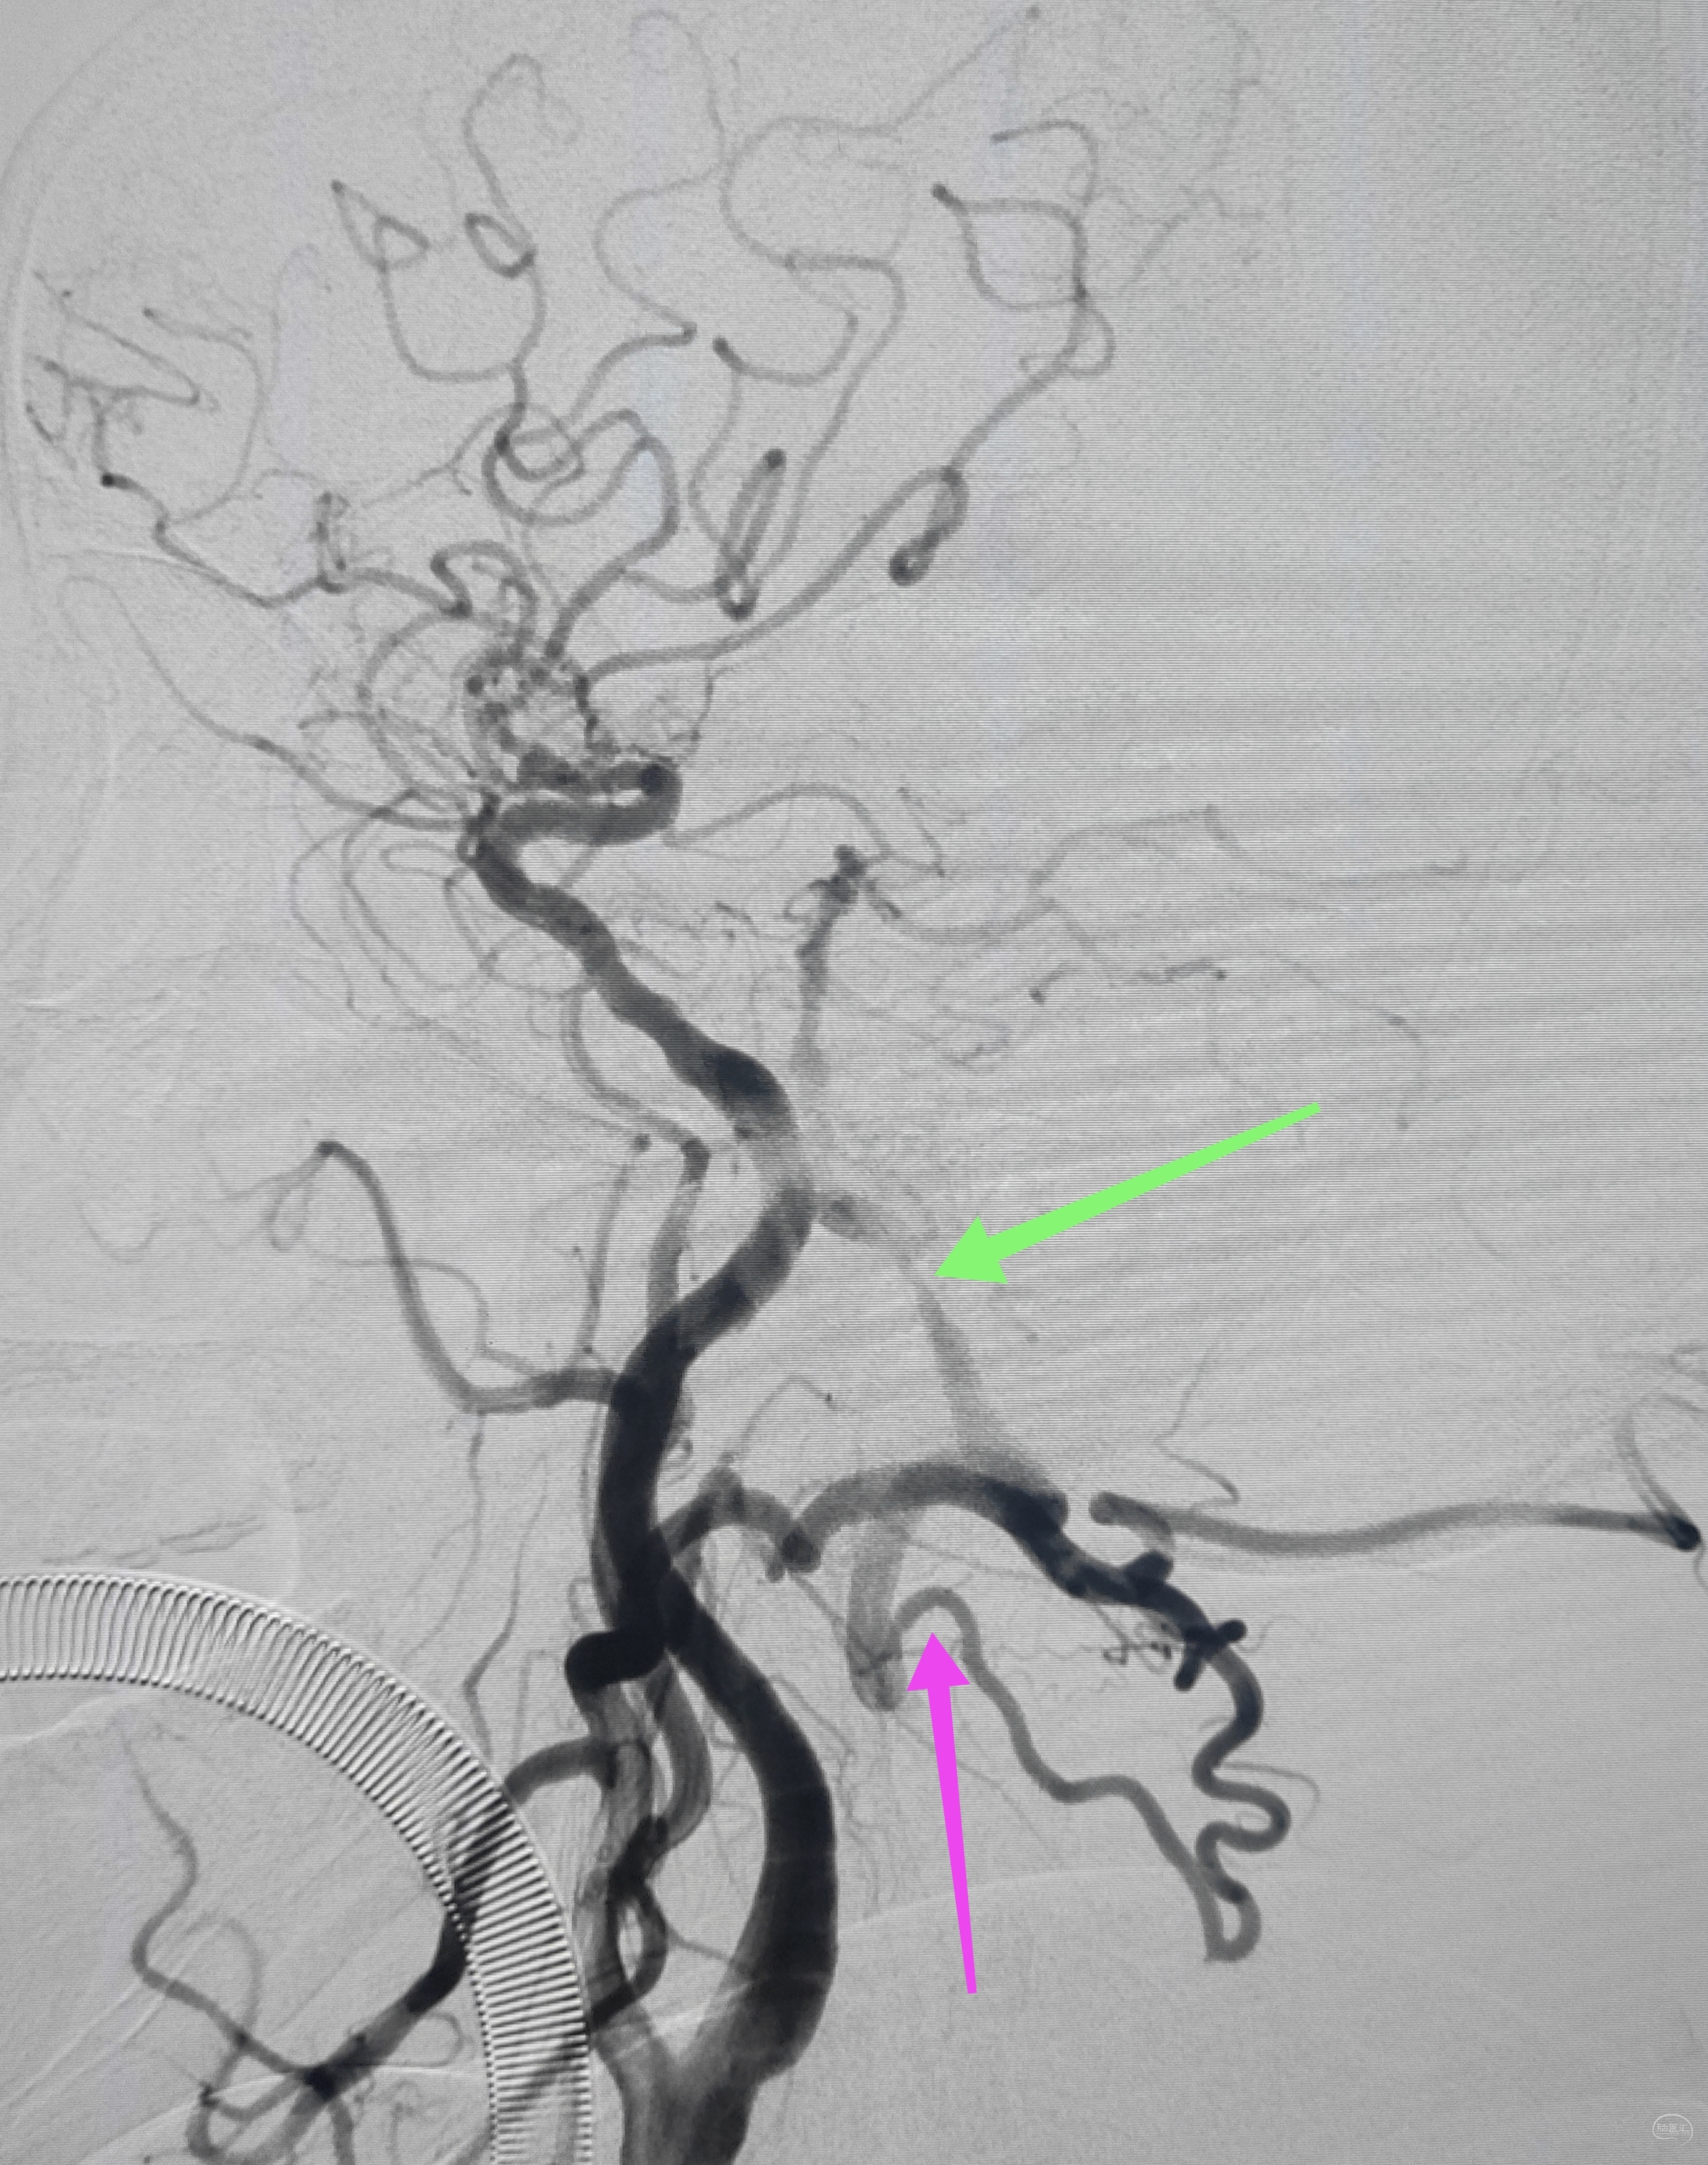

右侧颈总动脉正侧位造影:意料之外的是,枕动脉通过肌支与右侧椎动脉吻合(紫色箭头),像极了《大风吹》的歌词“借一杯天上的水”,源源不断进行着血流的补充。但是好景不长,同侧V4段明显狭窄,无情的设置了第二道坎(绿色箭头)。

左侧颈总动脉造影:颅内床突段以远基本闭塞,仅残涓涓细流,血供极差,脑膜中动脉瘤仅少量代偿,确实不容易,这估计就是想来搭桥的初衷了吧。

术后即刻造影,右侧椎动脉显影佳,并向左侧前循环代偿供血良好